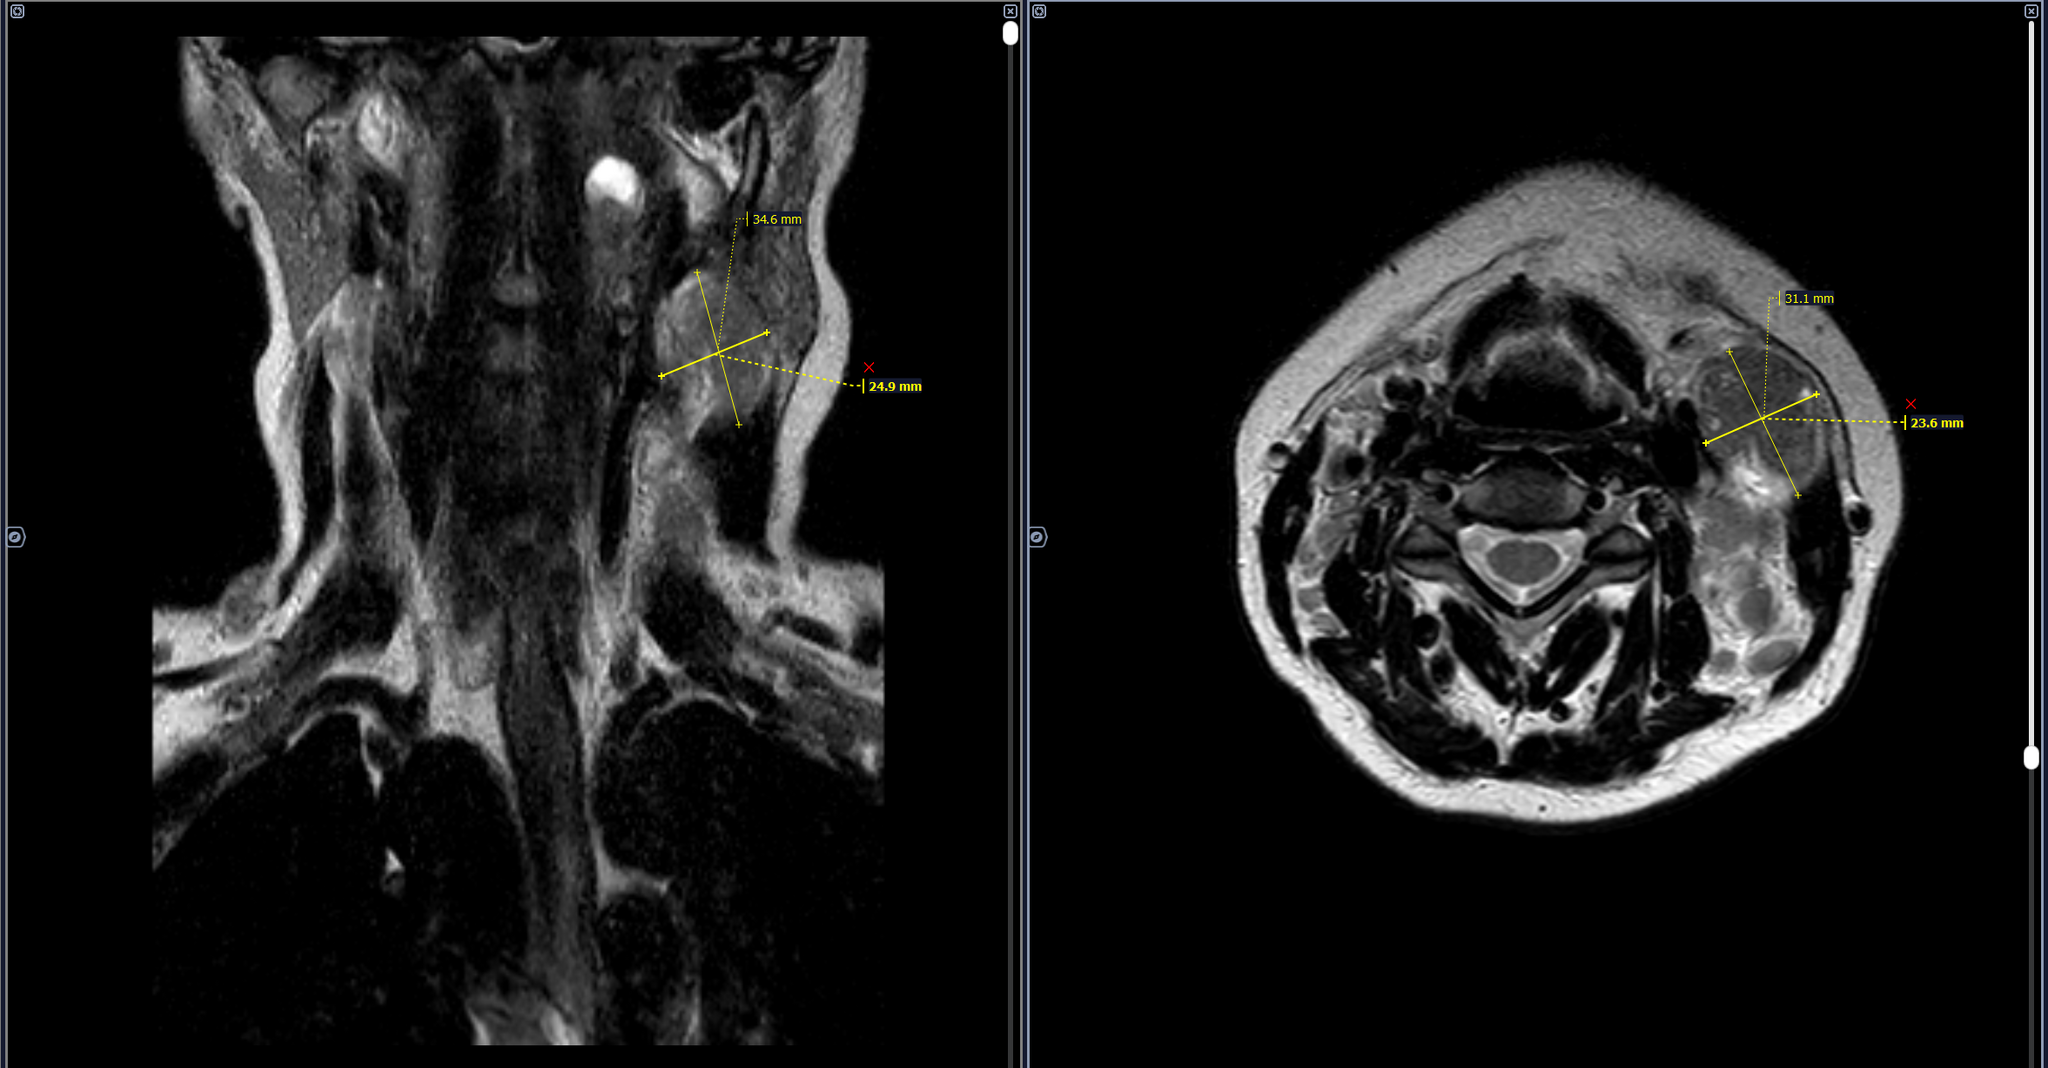

В левом окологлоточном пространстве определяется объемное образование овоидной формы, неоднородной кистозно-солидной структуры, с неоднородным контрастированием, размерами 3,4х2,4х2,3 см.

Определяются увеличенные лимфоузлы боковых поверхностей шеи неоднородной структуры, без врастания в сосуды, размерами до 1,9х1,0х2,0 см справа и до 2,9х2,4х2,4 см слева, с неоднородным контрастированием.

Заключение: МР-картина шейной лимфаденопатии - наиболее соответствует mts. Образование в левом окологлоточном пространстве: злокачественное новообразование/крупный mts в лимфоузел.